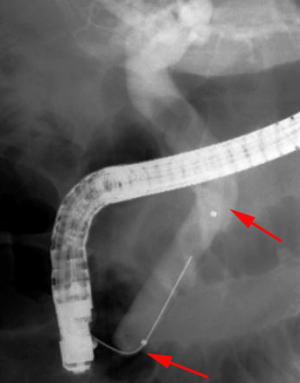

【EPLBD】 |

総胆管に15mm大の胆管結石を2個認めています(矢印)。 |

口径15~18mmの大口径拡張バルーンを用いて十二指腸乳頭(胆管の出口)の拡張術を実施しました。 |

矢印の間が拡張バルーンです。 |

乳頭拡張後に採石用のバスケット(金属線の器具)を用いて結石を破砕することなく除去しました。 |

除去した結石です。この方法では結石を破砕しなくて済むため、1回の処置でほぼすべての結石を除去することができます。 |